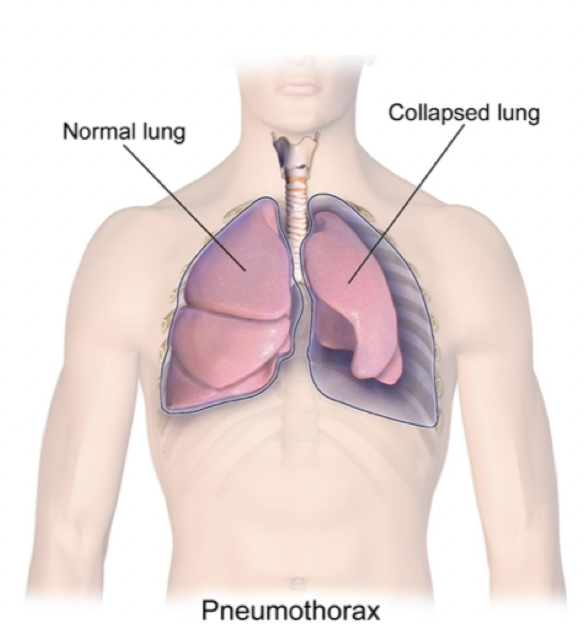

Hva er pneumothorax?

Luft i pleurahulen - kan komme fra lungen eller utenifra (som regel et hull i lungen)

• Normalt så er trykket litt lavere i pleurahulen enn i luftveiene og omgivelsene (vakuum som holder lungen i vegg)

• Ved pneumothorax blir trykket i luftveiene det samme som i pleurahulen –> lungen kollapser